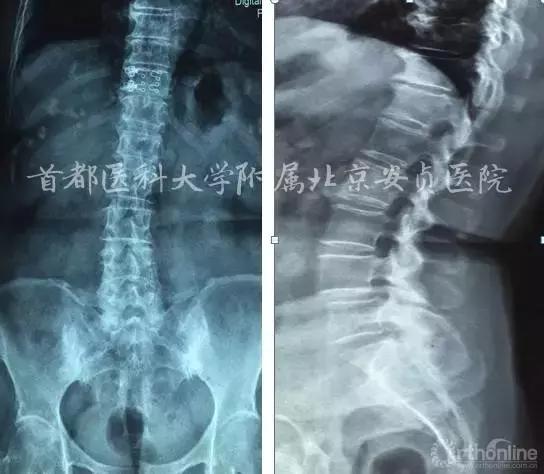

主诉:双下肢麻木无力6个月,颈臂疼痛加重2个月。

现病史:患者6个月前行走时无明显诱因出现双下肢无力、易摔倒、踩棉感,最远可行走50米,伴双上臂外侧疼痛,双侧小腿及足部感觉麻木。胸腹部束带感,无晕厥及意识障碍。近2月感颈后部、双上臂、腰部、骶尾部疼痛、双下肢麻木无力症状加重,行走约20米后出现胸憋气紧,腰背渐前倾不能挺直。

查体:下颈段棘突及椎旁压痛。四肢肌张力不高。双上臂外侧肌肉轻压痛,双侧肱二头肌、桡侧伸腕肌、肱三头肌肌力V级,双手握力V-。双侧Hoffman征(+)。双上肢反射正常。双下肢肌力V级。双侧膝腱反射、跟腱反射亢进,双侧巴氏征阳性。

颈椎JOA评分10分,颈部、双上臂疼痛VAS评分8分。

脊髓型颈椎病、颈椎间盘突出症、腰4滑脱(l度)、腰椎管狭窄、高血压病、冠心病。

本例影像学检查结果示C3-4,C5-6及C6-7均有硬膜囊受压,但是结合症状、体征、高龄,我们选择C5-6为责任节段,进行了针对性的减压,取得了良好的效果。